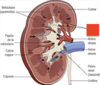

* a. cystique (branche de a. hépatique d.)

33

A. gastro-duodénale

branch of CHA that goes down

34

#14

A. gastrique d.

35

A. hépatique g. et d.

36

#13